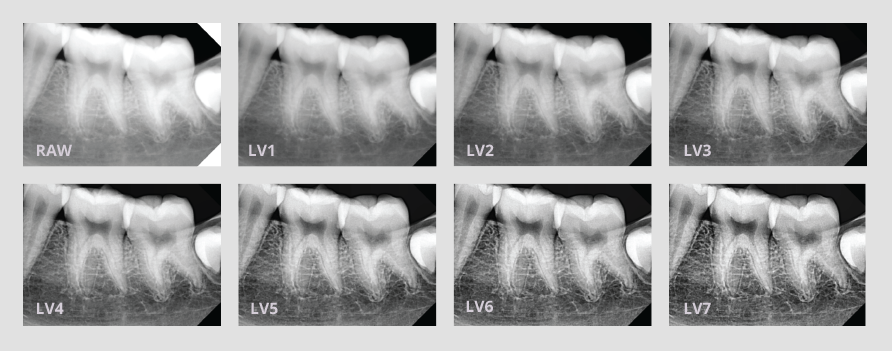

NUEVOS FILTROS DE CONTRASTE

Cuenta con 7 nuevos filtros de contraste para encontrar la imagen perfecta. Los filtros de más contrastes se pueden utilizar para periodoncia, mientras que los filtros con menor contraste puede utilizarlos para la detención y odontología restauradora.